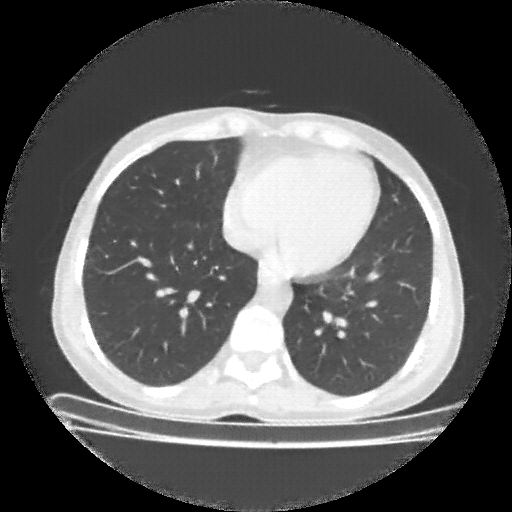

Original NATIVE CT scan (input)

Reconstructed NATIVE CT scan (cycle consistency)

Original VENOUS CT scan

Generated VENOUS CT scan (A→B translation)